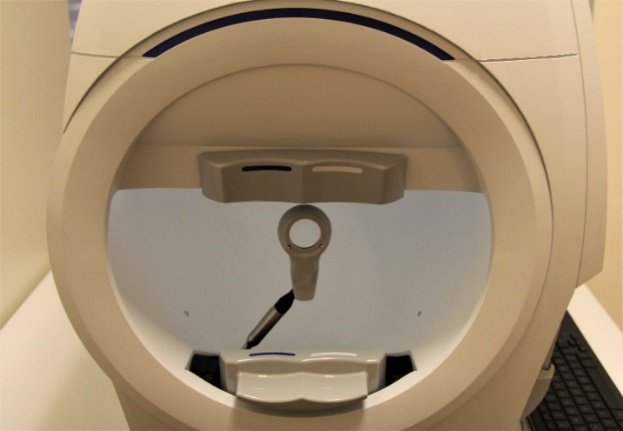

The device used to test the visual field is called a perimeter, and visual field testing is also called perimetry. There are several types of perimeters available, and each has different types of test patterns and stimuli. The testing involves the patient looking into the perimeter bowl, while focusing (fixating) on a central point. Different types of target light (the stimulus) are then projected at random points in the perimeter and the patient clicks a button when a target light is seen. The visual field is then mapped out and displayed.

Visual field testing is a simple test and usually takes just a few minutes to perform on an eye. Because of the central role that visual field testing plays in glaucoma management, it is important that patients undergo the appropriate type of testing at regular intervals, usually every few months, in order to ensure accuracy.

The two main visual field tests that we perform on patients are Standard Automated Perimetry (SAP) and Frequency-Doubling Perimetry (FDP). SAP functions better to monitor disease progression and FDP is more useful for early disease detection.